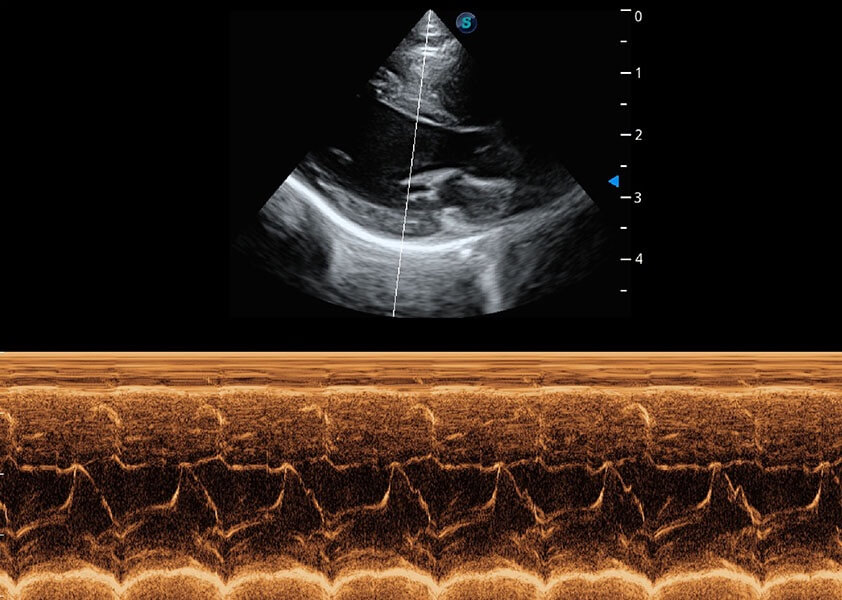

• AMM 解剖M型

通过360度任意调节3条M型取样线,在同一心动周期上观察心脏不同位置的运动曲线,得到准确的心功能测量数据,有效评估心肌运动及左心室功能。

(犬)乳头肌短轴

(猫)二尖瓣M型